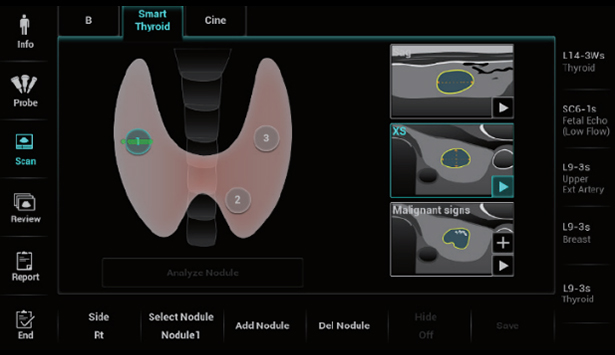

Resona I9 provides comprehensive clinical solutions for dedicated applications. Based on in-depth insights into different clinical scenarios, it delivers innovations that give users extreme clarity, outstanding intelligence and enhanced diagnostic confidence.